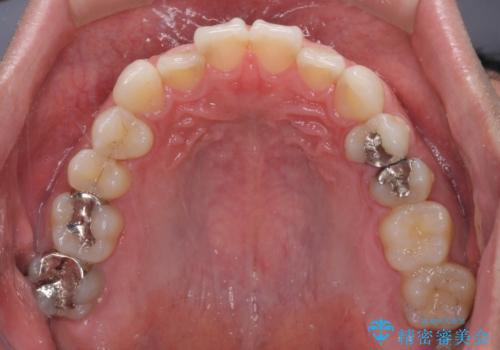

- 上下前歯の叢生を気にして来院された患者様です。

費用を抑え、期間もあまりかけずに治療をしたいとのことで、インビザライン・ライトを用いて矯正治療を行うこととしました。

インビザライン・ライトは、製作できるアライナーの枚数に制限があるため、移動可能な量に限りがあります。

一方で、半年から1年程度で治療を終えることができるため、軽度の歯列不正の患者様には大変お勧めです。